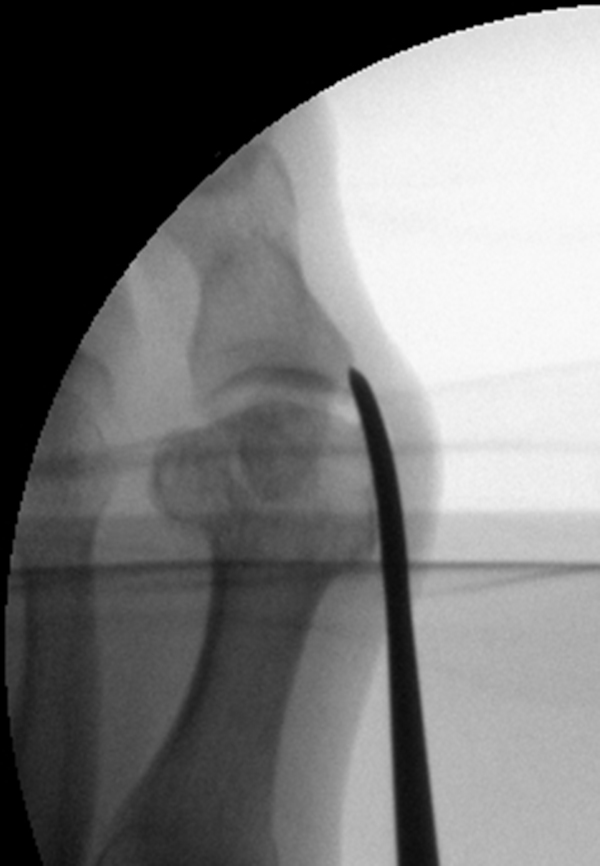

• Positionierung des Bildwandlers: 90° Winkel zum Os metatarsale I. Benötigt wird die Durchleuchtung des Vorfußes a.p., seitlich und schräg.

Operationstechnik

Der von Isham/Reverdin beschriebenen minimal invasiven Technik zur Korrektur einer Hallux valgus Deformität liegen 4 Operationsschritte zu Grunde:

2. Subcapitale intraartikuläre Osteotomie

Die Folge der Operationsschritte sollte strikt von 1. - 4. erfolgen, da ansonsten die mediale Closing Wedge Osteotomie bei vorzeitigem lateralem Release und/oder Akin Osteotomie nicht geschlossen werden kann. Nach der von Isham beschriebenen Originaltechnik finden Implantate keine Anwendung, zur Sicherung und besseren Fixation können osteosynthetische Verfahren angewandt werden (siehe auch Fehler, Gefahren und Komplikationen).